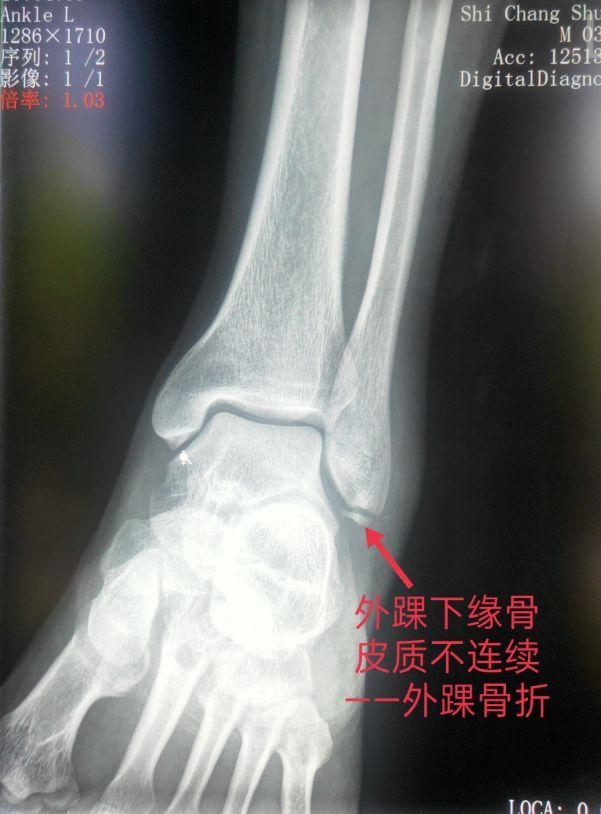

四、踝关节部位的骨折、脱位X线片

车祸、摔跤、跌倒都会造成骨折或脱位。以踝部、距骨、跟骨多见。

脚踝是哪个部位图解,脚踝是哪个部位图解视频(学习《X线读片指南》骨、关节系统——踝关节)